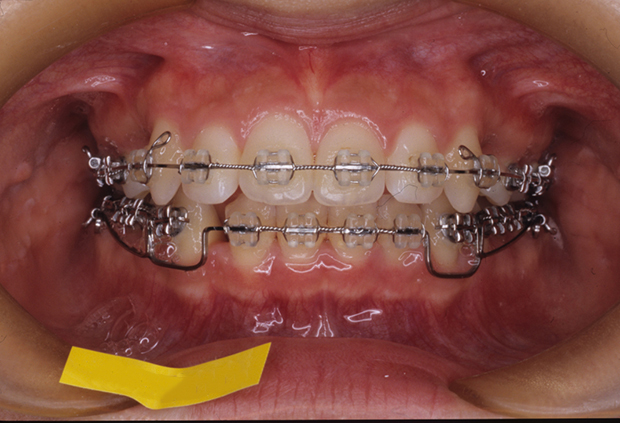

【開咬】上顎前突 抜歯 表側マルチブラケット装置

| 主訴 |

前歯で噛めない |

||

|---|---|---|---|

| 診断名 |

下顎前歯1歯先天性欠如を伴う開咬 |

||

| 年齢 | 21歳 | 性別 | 女性 |

| 治療に用 いた装置 |

唇側マルチブラケット装置 (メタルワイヤー) | 抜歯部位 | 上顎両側第一小臼歯 下顎右側第一小臼歯 |

| 治療期間 ・回数 |

2年7か月・31回 | 治療費 概算 |

約75万円 (調整料を含む) |

| 治療内容 詳細 |

患者様は開咬および上顎前突により前歯で噛めず、困っていました。治療を行うことにより唇も閉じやすくなり、麺類が噛み切れるようになったとのことです。 |

||

| リスク・ 副作用 |

装置による違和感、疼痛、歯根吸収など |

||